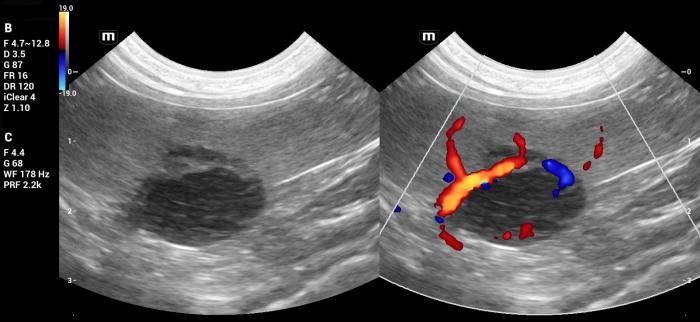

El Doppler color mostró vascularización positiva, principalmente periférica, sin patrones aberrantes evidentes (Figura7).

La masa deformaba la arquitectura de la cola esplénica y mostraba vascularización Doppler color positiva, observándose un vaso de gran calibre atravesando toda la masa, sin alteraciones evidenciables (Figura14). No se identificaron otras lesiones esplénicas focales ni alteraciones compatibles con metástasis.

- Vascularización Doppler color positiva (Figura 18-19).

La lesión deformaba la morfología de la cola esplénica y mostraba señal Doppler color positiva, principalmente periférica (Figura25).